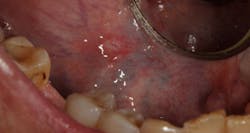

- 80% of canker sores are minor aphthous ulcers. These appear as round white lesions 2 mm to 8 mm in size, surrounded by a thin red halo usually occurring on nonkeratinized oral mucosa with a duration time of 10 to 14 days (figure 1).

Figure 1: Minor aphthous ulcer